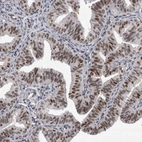

Immunohistochemical staining of human Fallopian tube shows moderate nuclear positivity in glandular cells.